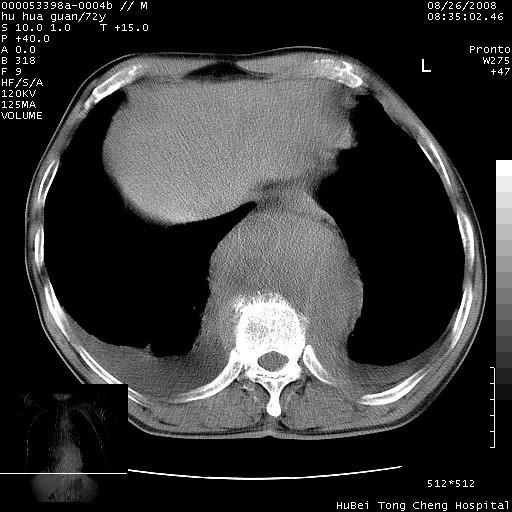

考虑胸主动脉下段夹层破裂。

考慮夾層動脈瘤破裂可能,建議增強掃描。

可以明确的说。肯定不是主动脉夹层破裂出血!考虑为淋巴瘤或间叶组织来源的恶性肿瘤可能性大。右肺小结节建议薄层观察,如能发现恶性征象,那椎前改变就考虑为转移所致。至于双侧少量胸水乃静脉血回流受阻所致。

降主动脉前移位,后纵隔占位

后纵隔占位,降主动脉前移位;双侧胸腔积液;应排外食管病变侵犯血管可能;